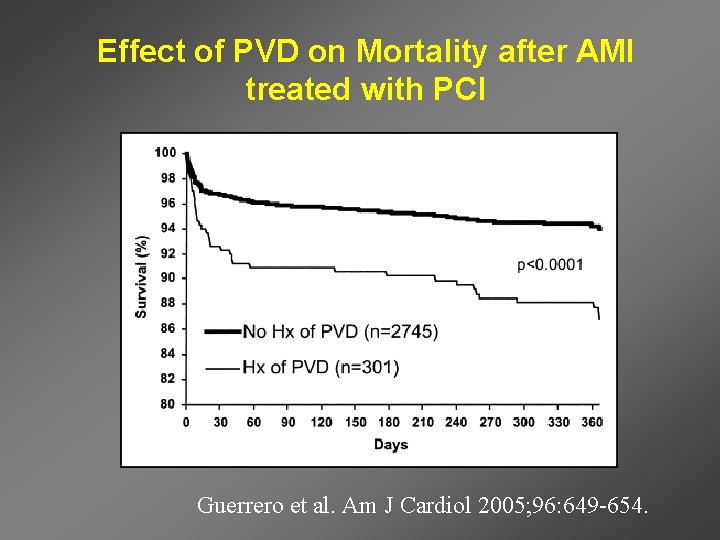

Effect of PVD on Mortality after AMI treated with PCI Guerrero et al. Am J Cardiol 2005; 96: 649 -654.